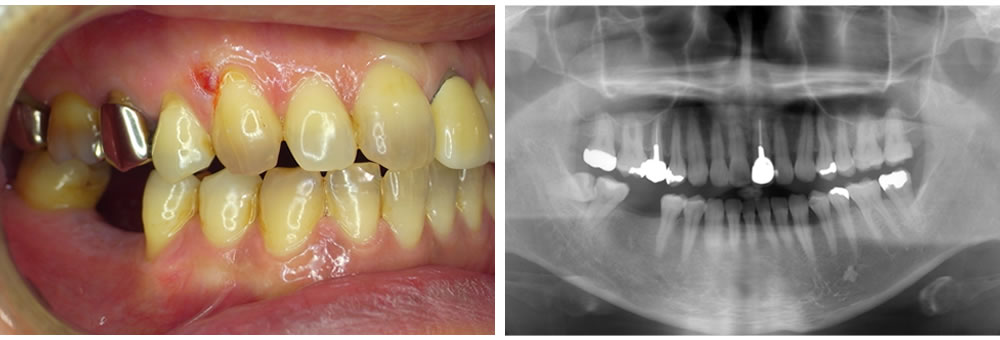

新津田沼歯科クリニック奏の杜で実際に行ったインプラント治療の症例をご紹介致します。

こちらの患者さまは、虫歯が原因で抜いた右下の歯が噛みづらくなったとのことでご来院されました。

歯を欠損した際に咬み合わせを回復するための治療方法は、大きく分けて以下の3つがあります。

今回は、患者様から『歯をあまり削りたくない。噛みごたえが欲しい。』というご要望がありましたので、それぞれの治療法についてしっかりと説明をした後、インプラント治療をすることになりました。

当院では、“リスクを最小限に抑えたインプラント治療”のために、事前に歯科用C Tを用いた画像診断・シミュレーションを必ず行なっております。

インプラントと顎骨が結合するまで待機した後、歯型を採取して最終的な上部構造(人工歯)を作製します。そして完成した上部構造をお口に装着して治療完了です。インプラント治療前後の写真はこちらです。